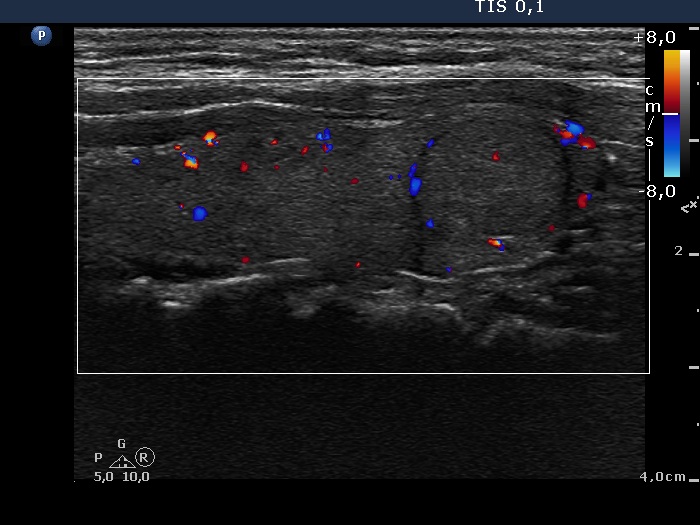

Discrete lesion or nodule in Hashimoto's thyroiditis - case 10 (95)

Follow-up investigation 3 months after the first visit (ultrasonographic picture 7)

Left lobe, longitudinal scan, color Doppler mode. The vascular pattern has not changed.